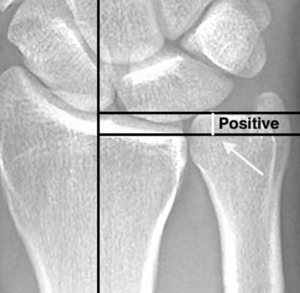

The syndrome occurs most commonly in patients with positive ulnar variance—a condition where the ulna bone is longer than the radius bone at the wrist joint. This anatomical variation causes increased pressure and mechanical stress on the ulnar side of the wrist during gripping and forearm rotation activities.

Positive Ulnar Variance: The most significant risk factor for ulnar impaction syndrome is positive ulnar variance, which can be either static (present at rest) or dynamic (occurring only during certain wrist positions or activities).This anatomical variation leads to excessive load bearing across the ulnar carpus, TFCC, and ulnar head.

Plain Radiographs: Initial imaging typically includes standard wrist X-rays to measure ulnar variance. Positive ulnar variance is the characteristic finding in ulnar impaction syndrome.